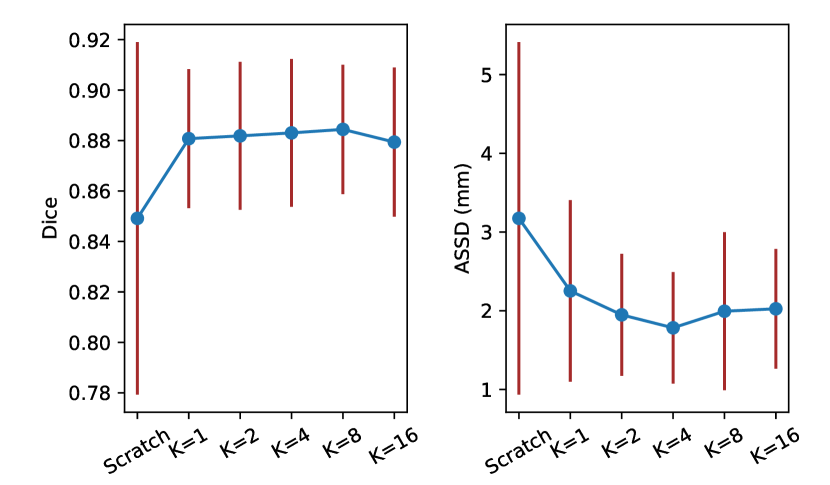

Effect of . To observe the effect of different values on performance of the pretrained model, we set it to 1, 2, 4, 8 and 16 respectively, and pretrained 3D U-Net [1] on PData-1K before training with the SegTHOR dataset. The pretrained models were compared with training from scratch. Quantitative evaluation results on the SegTHOR testing images are shown in Fig. 4. It can be observed that the average Dice value obtained by training from scratch was 84.92%, and all the variants of Volume Fusion outperformed it. Especially, led to an average Dice of 88.08%, and increasing to 2, 4 and 8 further improved the performance, respectively. obtained an average Dice of 87.94%, which was lower than those of the other values, but it was still much better than learning from scratch. In addition, Fig. 4 shows that achieved the lowest average ASSD value of 1.78 mm, compared with 3.17 mm obtained by training from scratch.